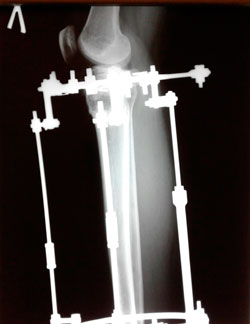

в процессе работы

image-26-06-20-10-31-14.jpg